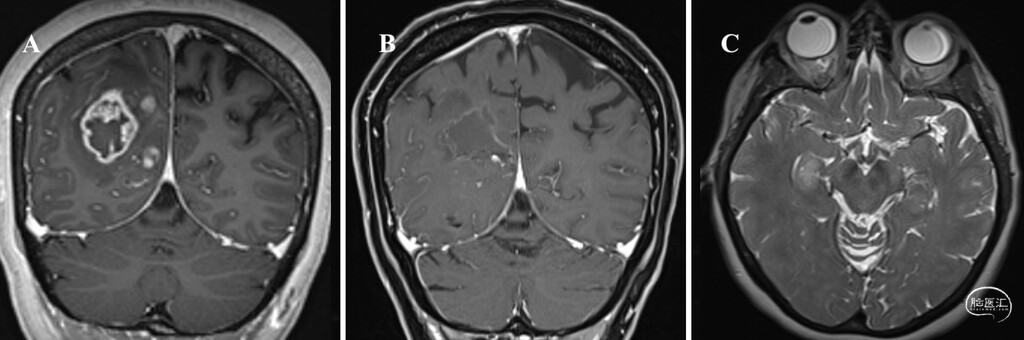

● 病例2:患者为58岁女性,因视力障碍就诊。MRI显示右侧顶枕叶有一大小为33×39×41毫米的不均匀强化肿块,T1加权像呈低信号,T2加权像呈高低混杂信号。同时在内侧颞叶发现另一处大小为17×12×10毫米的非强化病灶,T2加权像及FLAIR像呈高信号,考虑为多灶性GBM(图2)。

图2:病例2的术前及术后MRI。A:术前轴位增强T1加权像显示右侧顶枕叶强化性GBM。B:术后轴位增强T1加权像显示肿瘤全切,可见手术残腔且无残余强化。C:轴位T2加权MRI显示右侧海马区存在多灶性GBM远隔病灶,呈高信号并伴周围水肿,因位于功能区,后续采用LITT进行治疗。

图3:病例1术后MRI,显示肿瘤全切与消融效果。A:冠状位T2加权像可见右侧脑室旁及胼胝体前部病灶已完全消融,可见激光导管通道,左侧额叶病灶术后残腔提示肿瘤完整切除。B:冠状位增强T1加权像显示右侧脑室旁及胼胝体前部病灶完全消融,左侧额叶肿瘤全切,无强化残余肿瘤,证实两处多灶性病变均得到彻底治疗。

分期开颅切除+LITT:经神经肿瘤多学科会诊讨论,建议先切除右侧顶枕叶病灶,右侧内侧颞叶病灶待病理结果回报后再行处理。顶枕叶病灶切除术后,患者于术后第2天出院,术后MRI证实肿瘤全切(图2)。最终病理提示为IDH野生型GBM,遂对右侧内侧颞叶病灶行LITT,消融平均功率10.8瓦,持续3.5分钟。消融后24小时MRI体积分析显示EOA达120%。